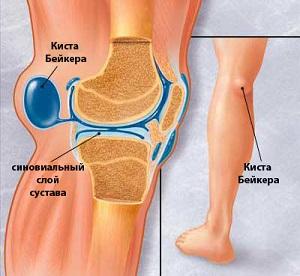

Это скопление синовиальной жидкости в межсухожильной сумке, находящейся в области подколенной ямки.

Эта патология также известна как грыжа или бурсит. Согласно международной классификации болезней (МКБ 10), ей присвоен код M71.2, что соответствует синовиальной кисте в подколенной области.

Фото кисты Бейкера под коленом наглядно иллюстрирует, каких размеров может достигать эта киста.